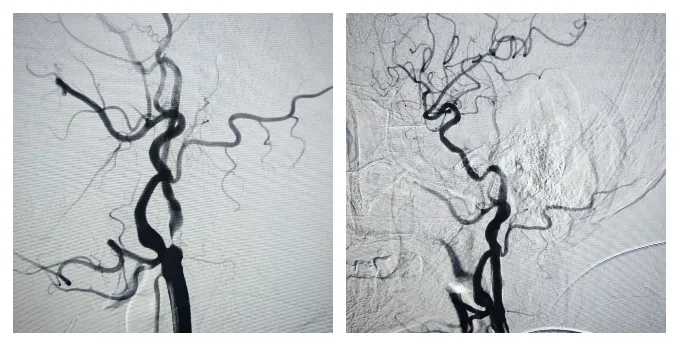

75岁男性患者,半个月前出现右侧肢体麻木伴僵硬抽搐症状,血管造影显示右侧颈内动脉C1段中度狭窄、左侧颈内动脉C1段重度狭窄,磁共振显示头颈部动脉硬化。五疗脑病科主任玉山带领团队对患者术前进行充分的评估及会诊,排除手术禁忌症,并与患者及家属充分沟通后,制定了详细的手术方案,成功完成颈动脉支架植入术。

手术前 手术后

手术过程顺利。术后患者血管开通良好,各项生命体征平稳,患者恢复达到预期。